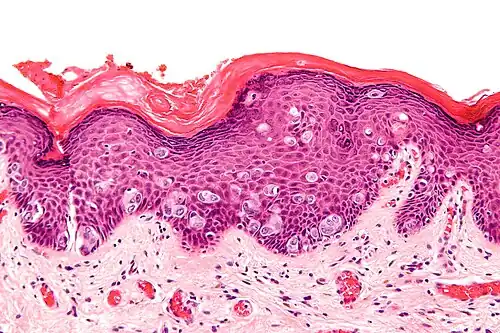

Micrograph of extramammary Paget's disease, H&E stain

H&E stained micrograph of Extramammary Paget's disease, showing Paget cells infiltrating the epidermis

EMPD occurs due to an invasion of the epidermis by Paget cells.[2] The cause of the disease is still under debate with recent research indicating that the disease may be associated with Toker cells.[13]

It is important to include that the lesion is associated with another cancer. A biopsy will establish the diagnosis. Punch biopsies are not effective in differentially diagnosing for EMPD and as a result, excisional biopsies of the affected area are taken [XX]. A positive test result for EMPD shows increased numbers of large polygonal cells with a pale bluish cytoplasm, large nucleus and nucleolus, infiltrating the epidermal layer.[7] These neoplastic cells can be found singly scattered or can appear in groups called nests.[7]